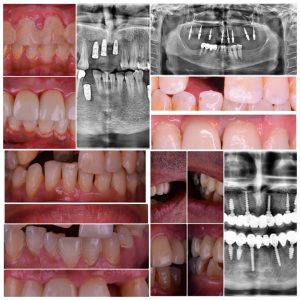

تبدأ خطوات زراعة الاسنان بالتشخيص السليم للحالة للتحقق من امكانية زراعة الاسنان بناء على كمية العظم المتبقية في جميع الاتجاهات

كالطول والعرض والسُمك حتى نتأكد إذا كان بإمكان العظم المتبقي احتواء الغرسة ام لا

وايضا يقوم طبيب الاسنان بالكشف من خلو العظم والفم من اية مشاكل كالأكياس الدهنية والالتهابات والاورام

والكشف عن الانسجة الحيوية بالمنطقة المحيطة بالغرسة لحمياتها وكل ذلك يتم التأكد منه بأخذ صورة اشعة ثلاثية الابعاد في مركز وندرز لطب الاسنان.

يقوم الطبيب ايضا خلال التشخيص بتحديد عدد الزرعات التي يحتاجها المريض

وما هي المشاكل الاخرى التي تحتاج الى علاج الاسنان من حشوات او علاج للعصب او علاج اللثة حتى يحصل المريض على أفضل نتيجة نهائية

وتأتي الخطوة الأهم بعد ذلك في اجراء عملية زراعة الاسنان

التي يقوم فيها الطبيب المعالج بكشف العظم من خلال اللثة وادخال الغرسة داخل عظام الفك

باستعمال ادوات خاصة للزراعة في اتجاه ووضع يسمح بالتركيب المثالي المطلوب بعد ان يتم وضع الغرسة داخل عظام الفك في وضع يسمح بالتركيب المثالي

يتم اغلاق الجرح ثم يتلقى المريض تعليمات هامة خلال فترة التعافي من الجراحة عليه اتباعها بحرص لتمام تعافيه.

في فترة تتراوح من 3 الى 6 اشهر يحدث التئام كلي بين العظم والزرعة

حيث يأتي بعد ذلك زيارتك الى طبيب الاسنان لأخذ مقاس الفكين بالزرعات باستخدام كاميرا ديجيتال صغيرة مخصصة لأخذ المقاسات داخل الفم

حتى يتم بناء التيجان او الجسور التي سوف توضع فوق الزرعة بدقة عالية جدا.